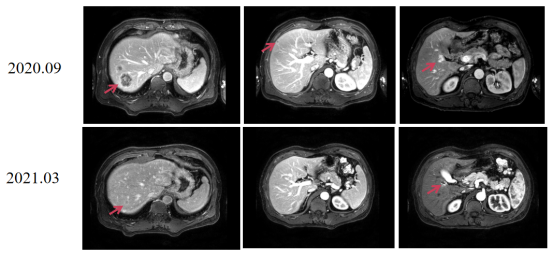

image.png

图4 影像评估提示直肠肿瘤较前缩小

图5 影像评估提示肝脏转移瘤较前缩小,靠近肝包膜表面小肿块消失

2021.04复查影像评估提示:肝右叶膈顶S7 及胆囊窝转移瘤较前减小,仍有活性。

图6 影像评估提示肝右叶膈顶S7 及胆囊窝转移瘤较前减小,仍有活性